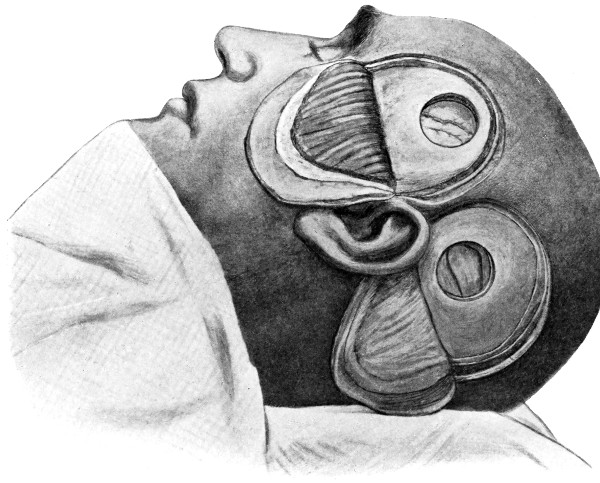

| 45-48. Intermusculo-temporal cerebral decompression | 122, 123 |

| 52 A and B. The operative treatment of middle meningeal hæmorrhage | 144, 145 |